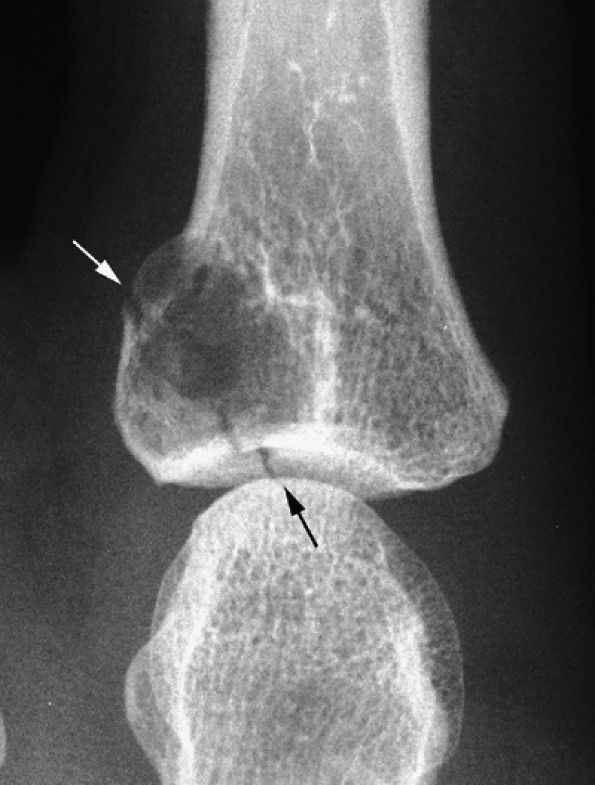

seen with synovial sarcomas. Bone and joint invasion is possible.168 Ultrasonography shows a nonspecific solid mass with a variable color Doppler signal. MR images are specific, depicting a well-defined mass with hemosiderin deposits. Typical signal void artifacts are seen on all sequences, particularly on gradient-echo images, and a more heterogeneous and predominantly low signal is found on T2-weighted images.162,166,169 The lesion typically enhances after intravenous injection of gadolinium (Fig. 11.74). The tendon sheath of the flexor digitorum tendons is usually partially or totally enveloped; the extensor tendons are less commonly involved. Some lesions may be more aggressive, and diffuse lesions are seen in multiple locations with invasion of both the flexor and extensor tendons (Fig. 11.75).170

FIGURE 11.73 ● Giant cell tumor of the tendon sheath. Lateral view radiograph shows a large mass of the palmar soft tissue (asterisk) and bone pressure erosion (arrows).